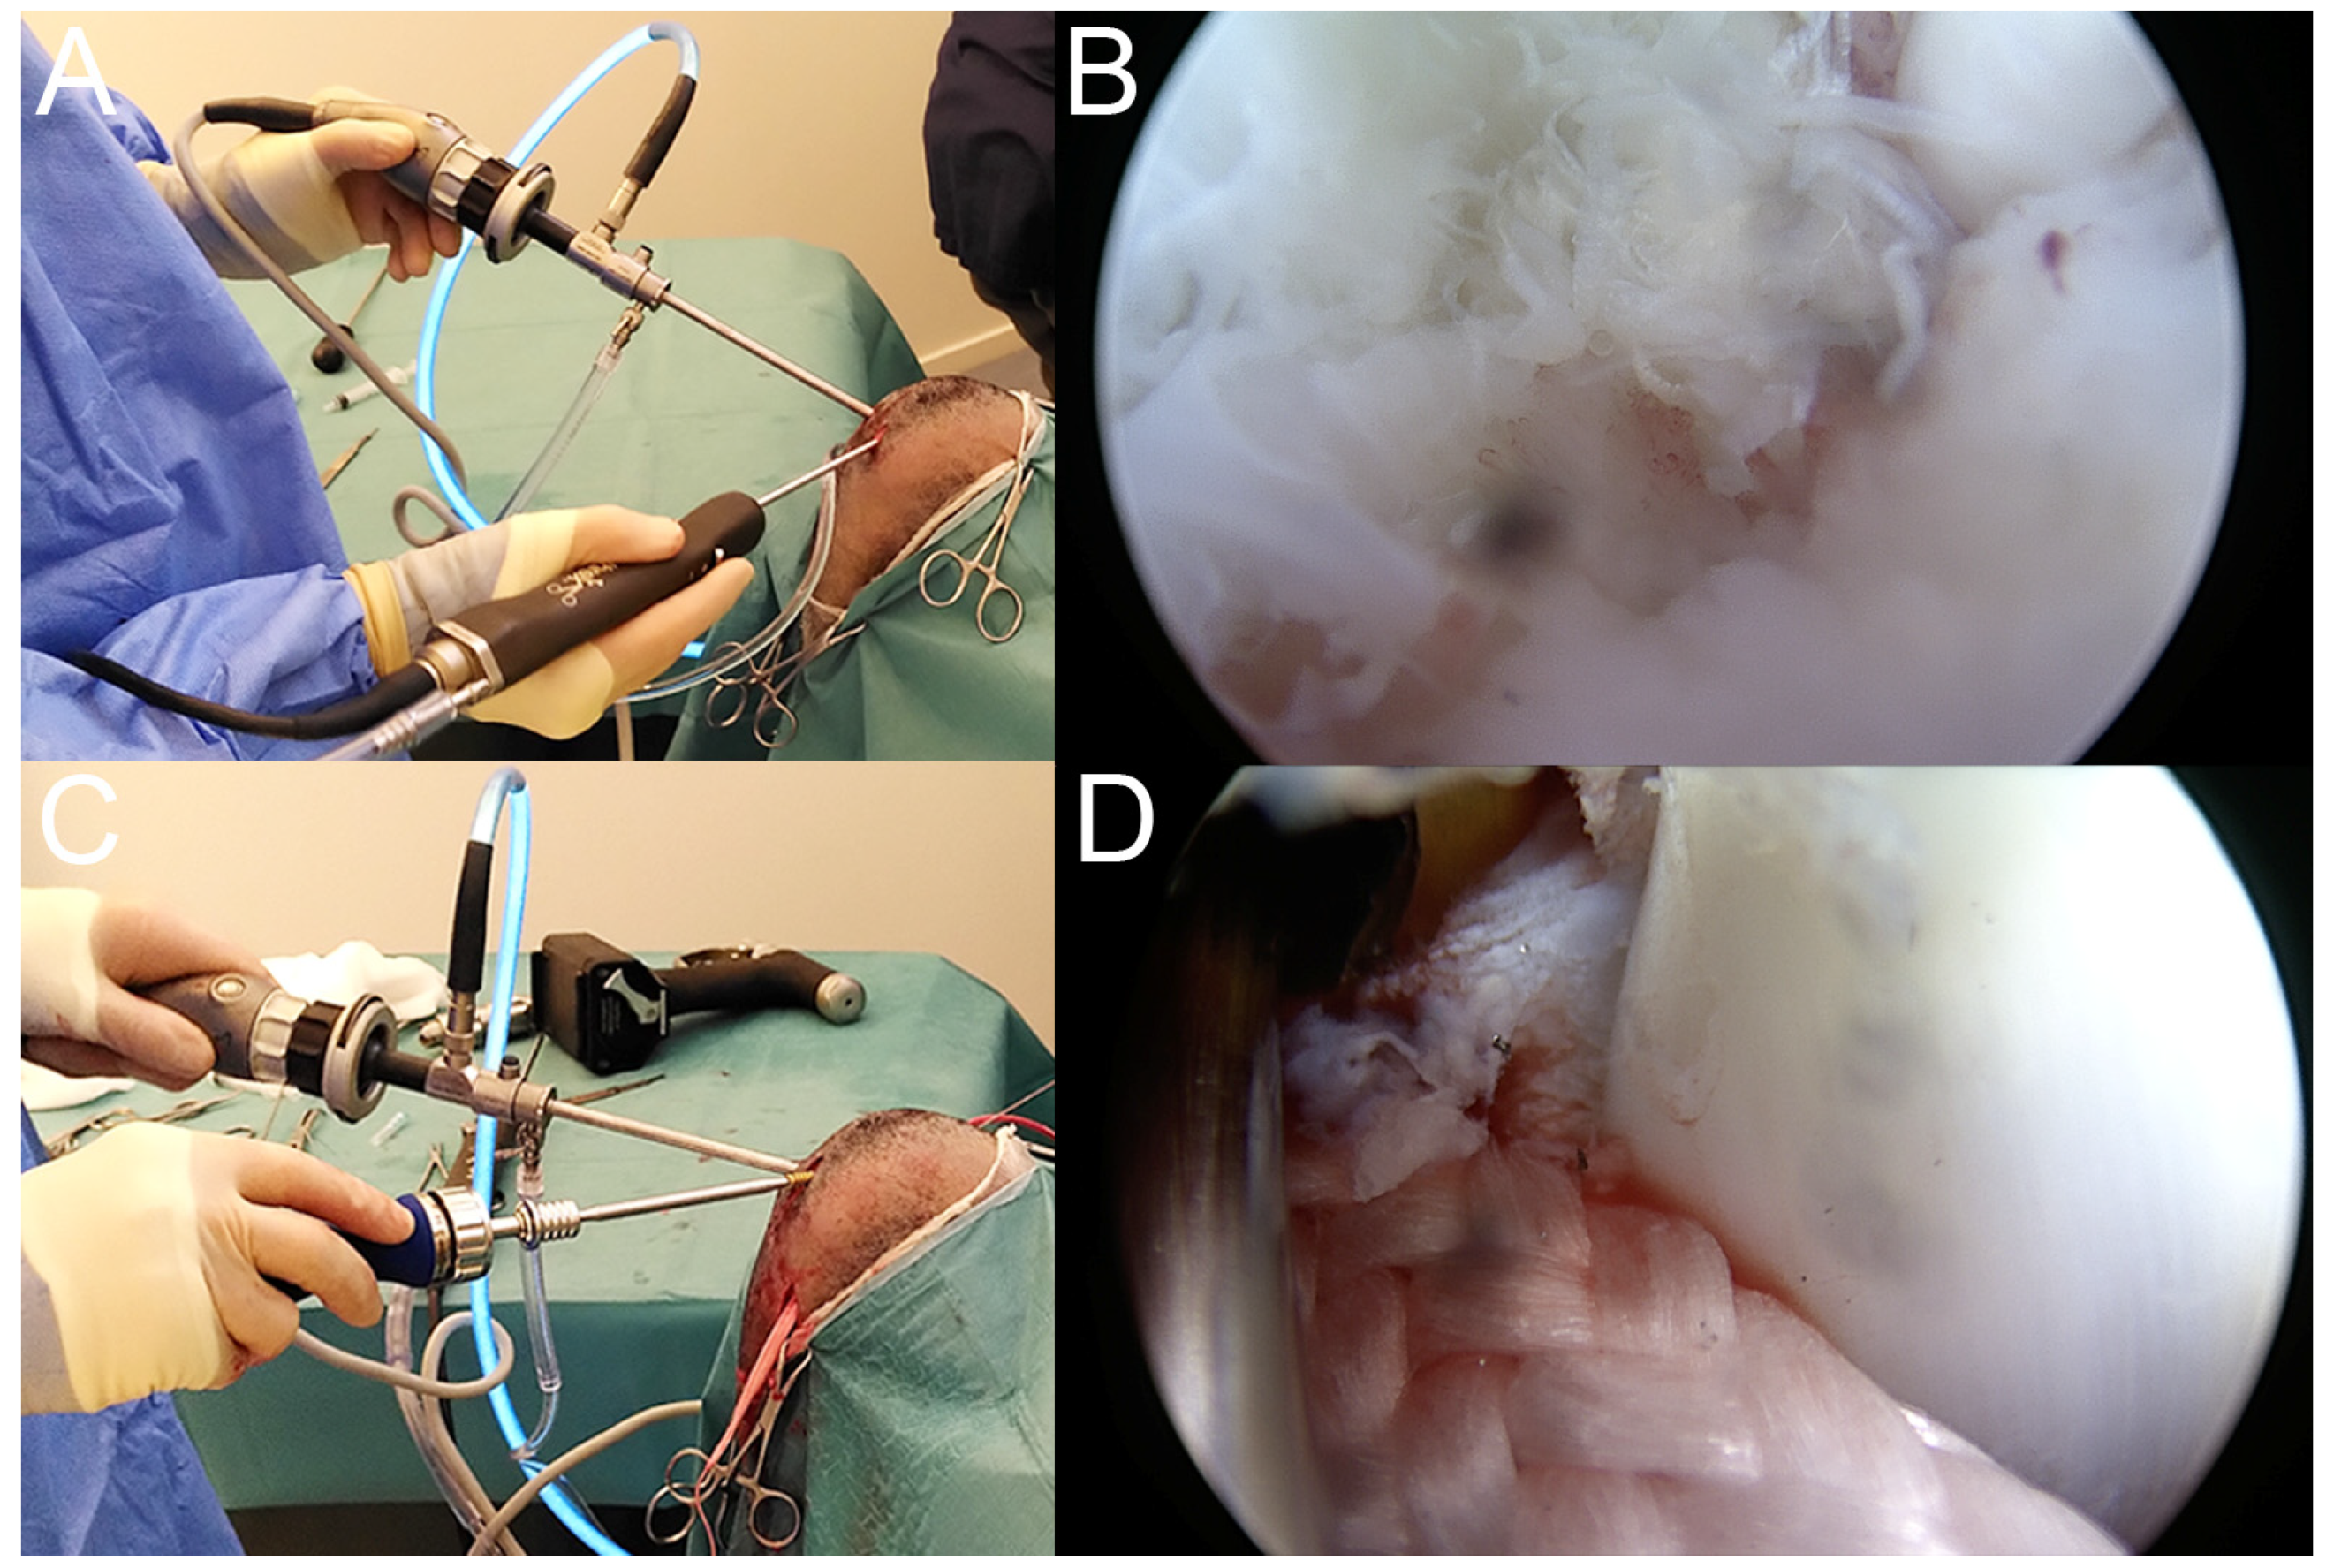

2.5. Immediate Postoperative Evaluation

3. Results